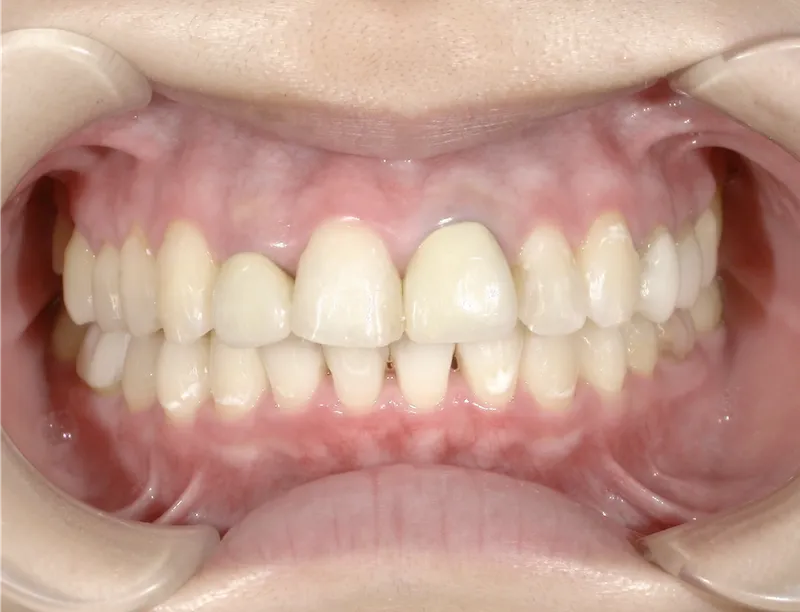

歯科の医療ホワイトニング

痛くない・しみないのに、45分で白くなる。